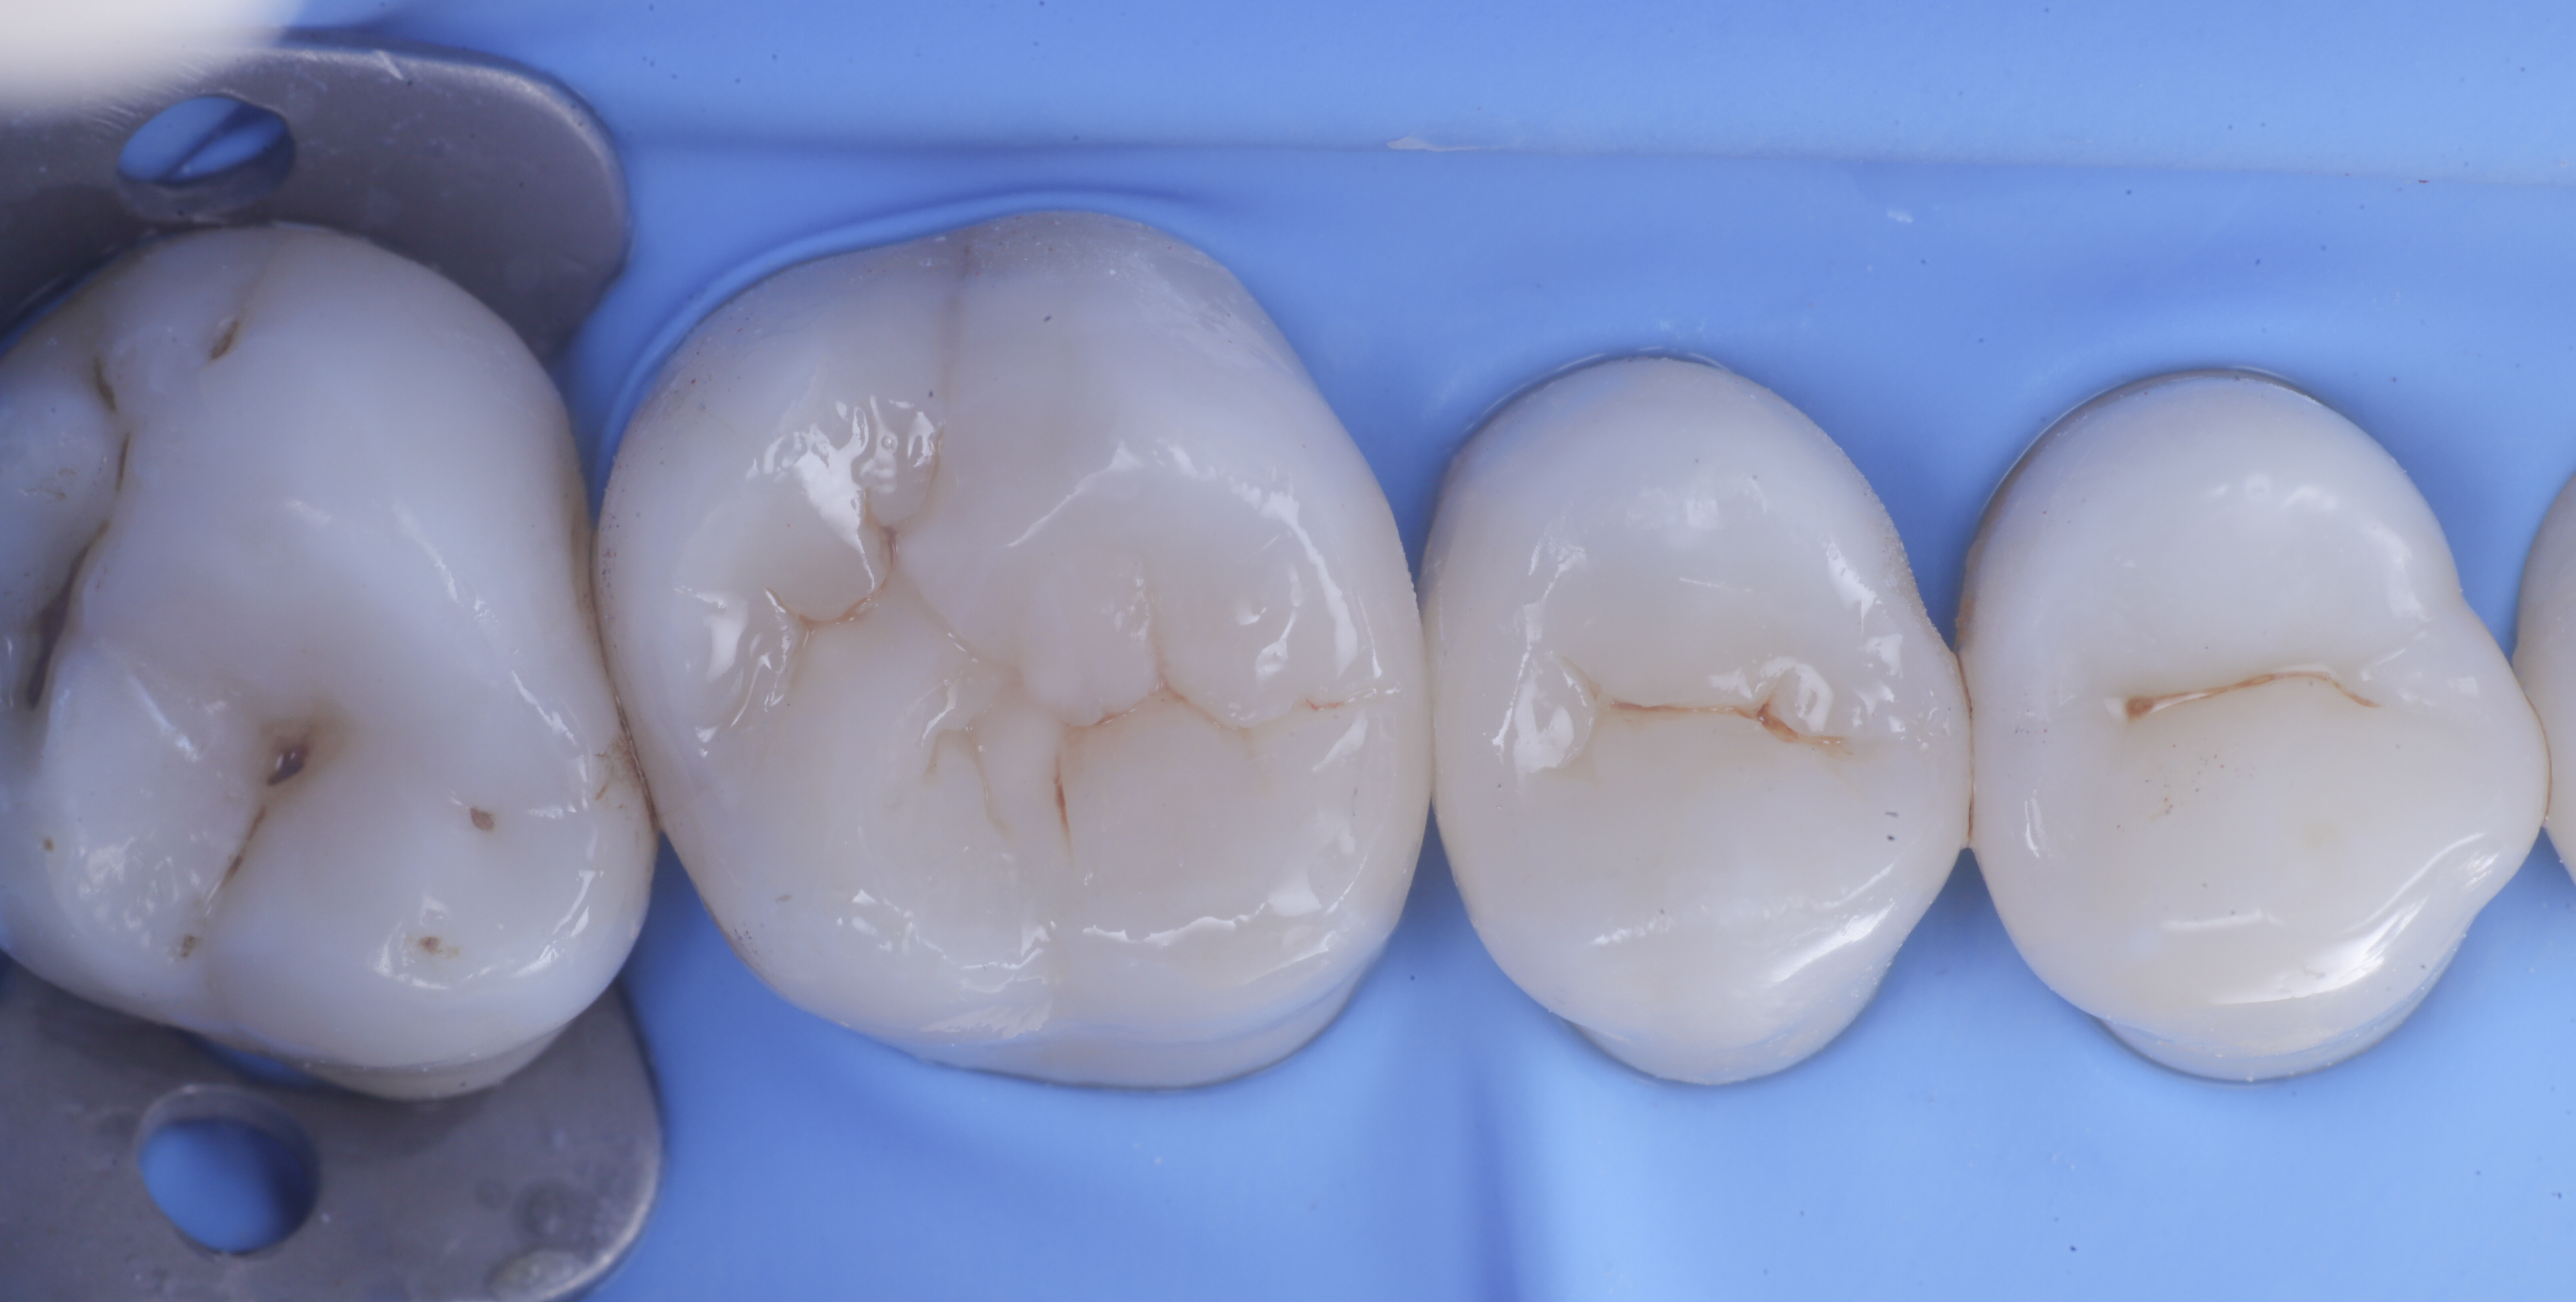

foto 1 Fotografia iniziale

Si presenta alla nostra attenzione per dolore in zona premolare e molare del primo quadrante. Dopo un’analisi clinica e strumentale con radiografie e test diagnostici, si evidenzia la necessità di sostituire le precedenti otturazioni in composito, al fine di consegnare un migliore punto di contatto (fenomeno dell’impact food).

Come spesso accade in queste circostanze si decide per il rifacimento di tali restauri sia su 1.6 che su 1.5.